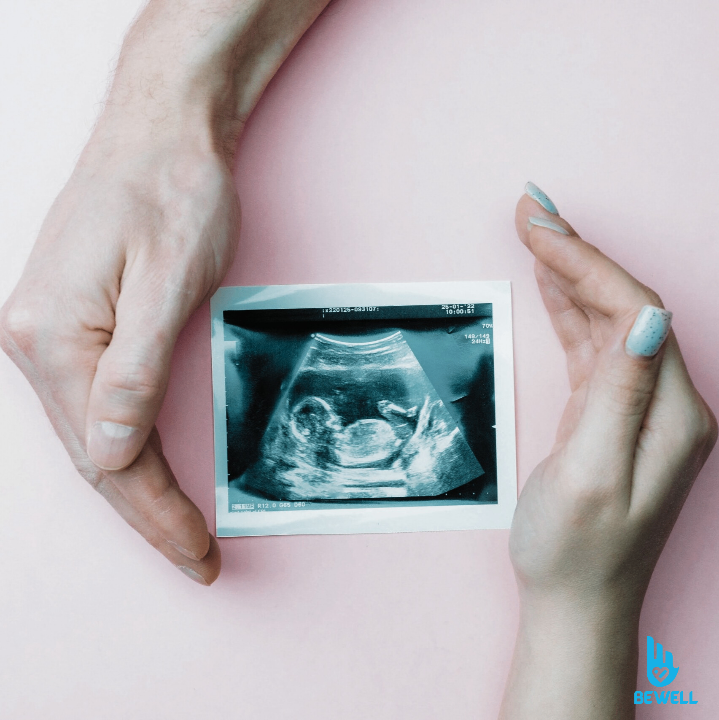

An NT scan (Nuchal Translucency scan) is a specialized prenatal ultrasound performed during the first trimester to assess the risk of chromosomal abnormalities, such as Down syndrome, Edwards syndrome and Patau syndrome.